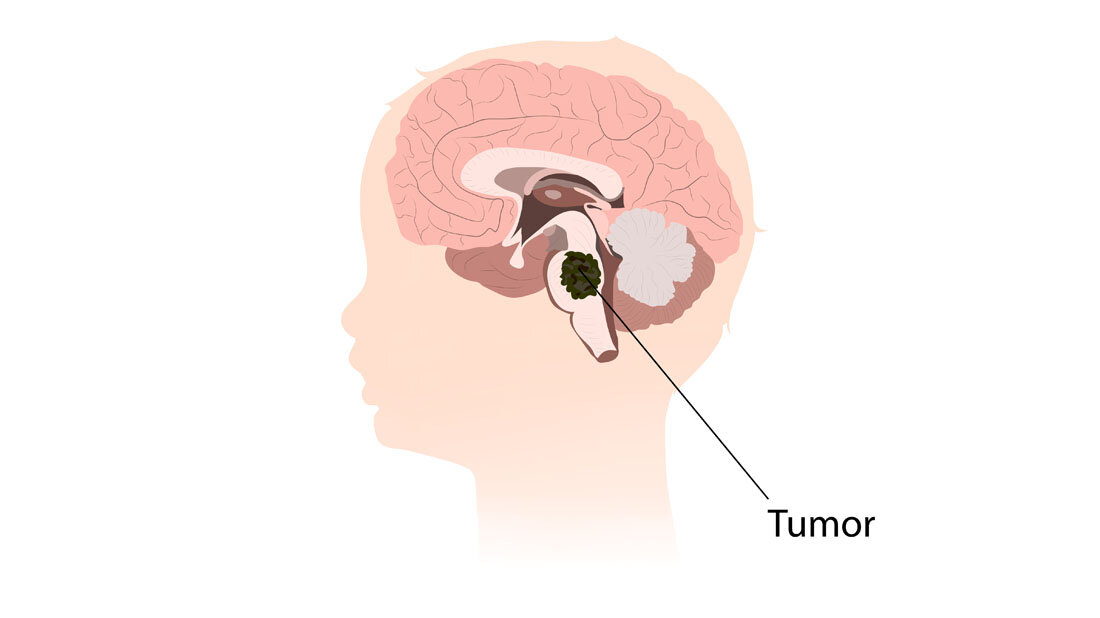

Diffuse Mittellinien-Gliome zählen zu den aggressivsten Hirntumoren. Sie treten meist bei Kindern und jungen Erwachsenen in der Nähe des Hirnstamms auf und sind daher operativ nur schwer zugänglich. Auch Chemo- oder Strahlentherapie sind nur begrenzt wirksam. Bei dieser Krebsart treten charakteristischerweise Mutationen im Gen für das Histon H3 (H3K27M) auf, einem Verpackungsprotein der DNA. Die Mutation lässt eine neuartige Proteinstruktur entstehen – ein so genanntes Neoepitop, das vom Immunsystem des Patienten als fremd erkannt werden kann.